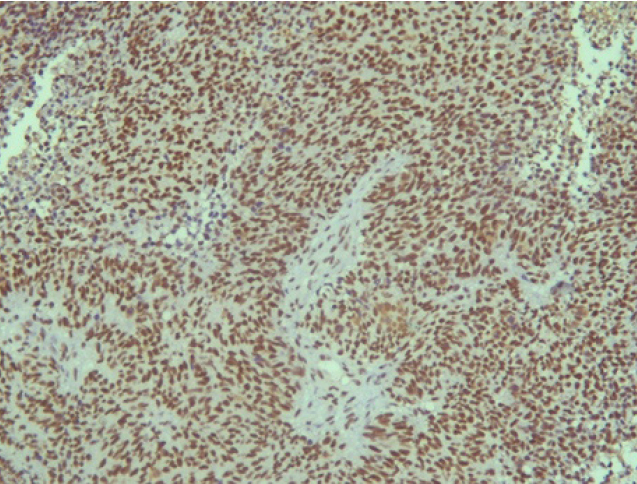

Поэтому при первичном гистологическом исследовании диагноз эстезионейробластомы был установлен только у 6 пациентов (66,6 %), у троих больных (33,4 %) были диагностированы другие формы злокачественного процесса, что не соответствовало клиническим проявлениям. Во всех случаях проводили иммуногистохимическое (ИГХ) исследование. ИГХ-исследование проводили на срезах с парафиновых блоков с использованием антител к Keratin.Pan (AE/AE3), CD45 (Cocktail), Synaptophysin (SP11), ChromograninA (SP12), CD56 (56C04), Ki-67 (30-9), p63 (7JUL)RTU, S100, INI1, CD99 (HO36-1.1). Также выполняли доставку с антителами к EMA (E29), TTF1 (8G7G3/1). В диагностических материалах была отмечена положительная экспрессия Synaptophysin, ChromograninA, CD56, Ki-67 (до 90% ядер), INI1 (рис. 2–6).

Рис. 2. Synaptophysin [SP 11] ×200

Рис. 3. Chromagranin A [SP 12] ×200

Рис. 4. CD 56 [56C04] ×200

Рис. 5. Ki-67 [30-9] (90%) ×200

Рис. 6. INI 1 ×200